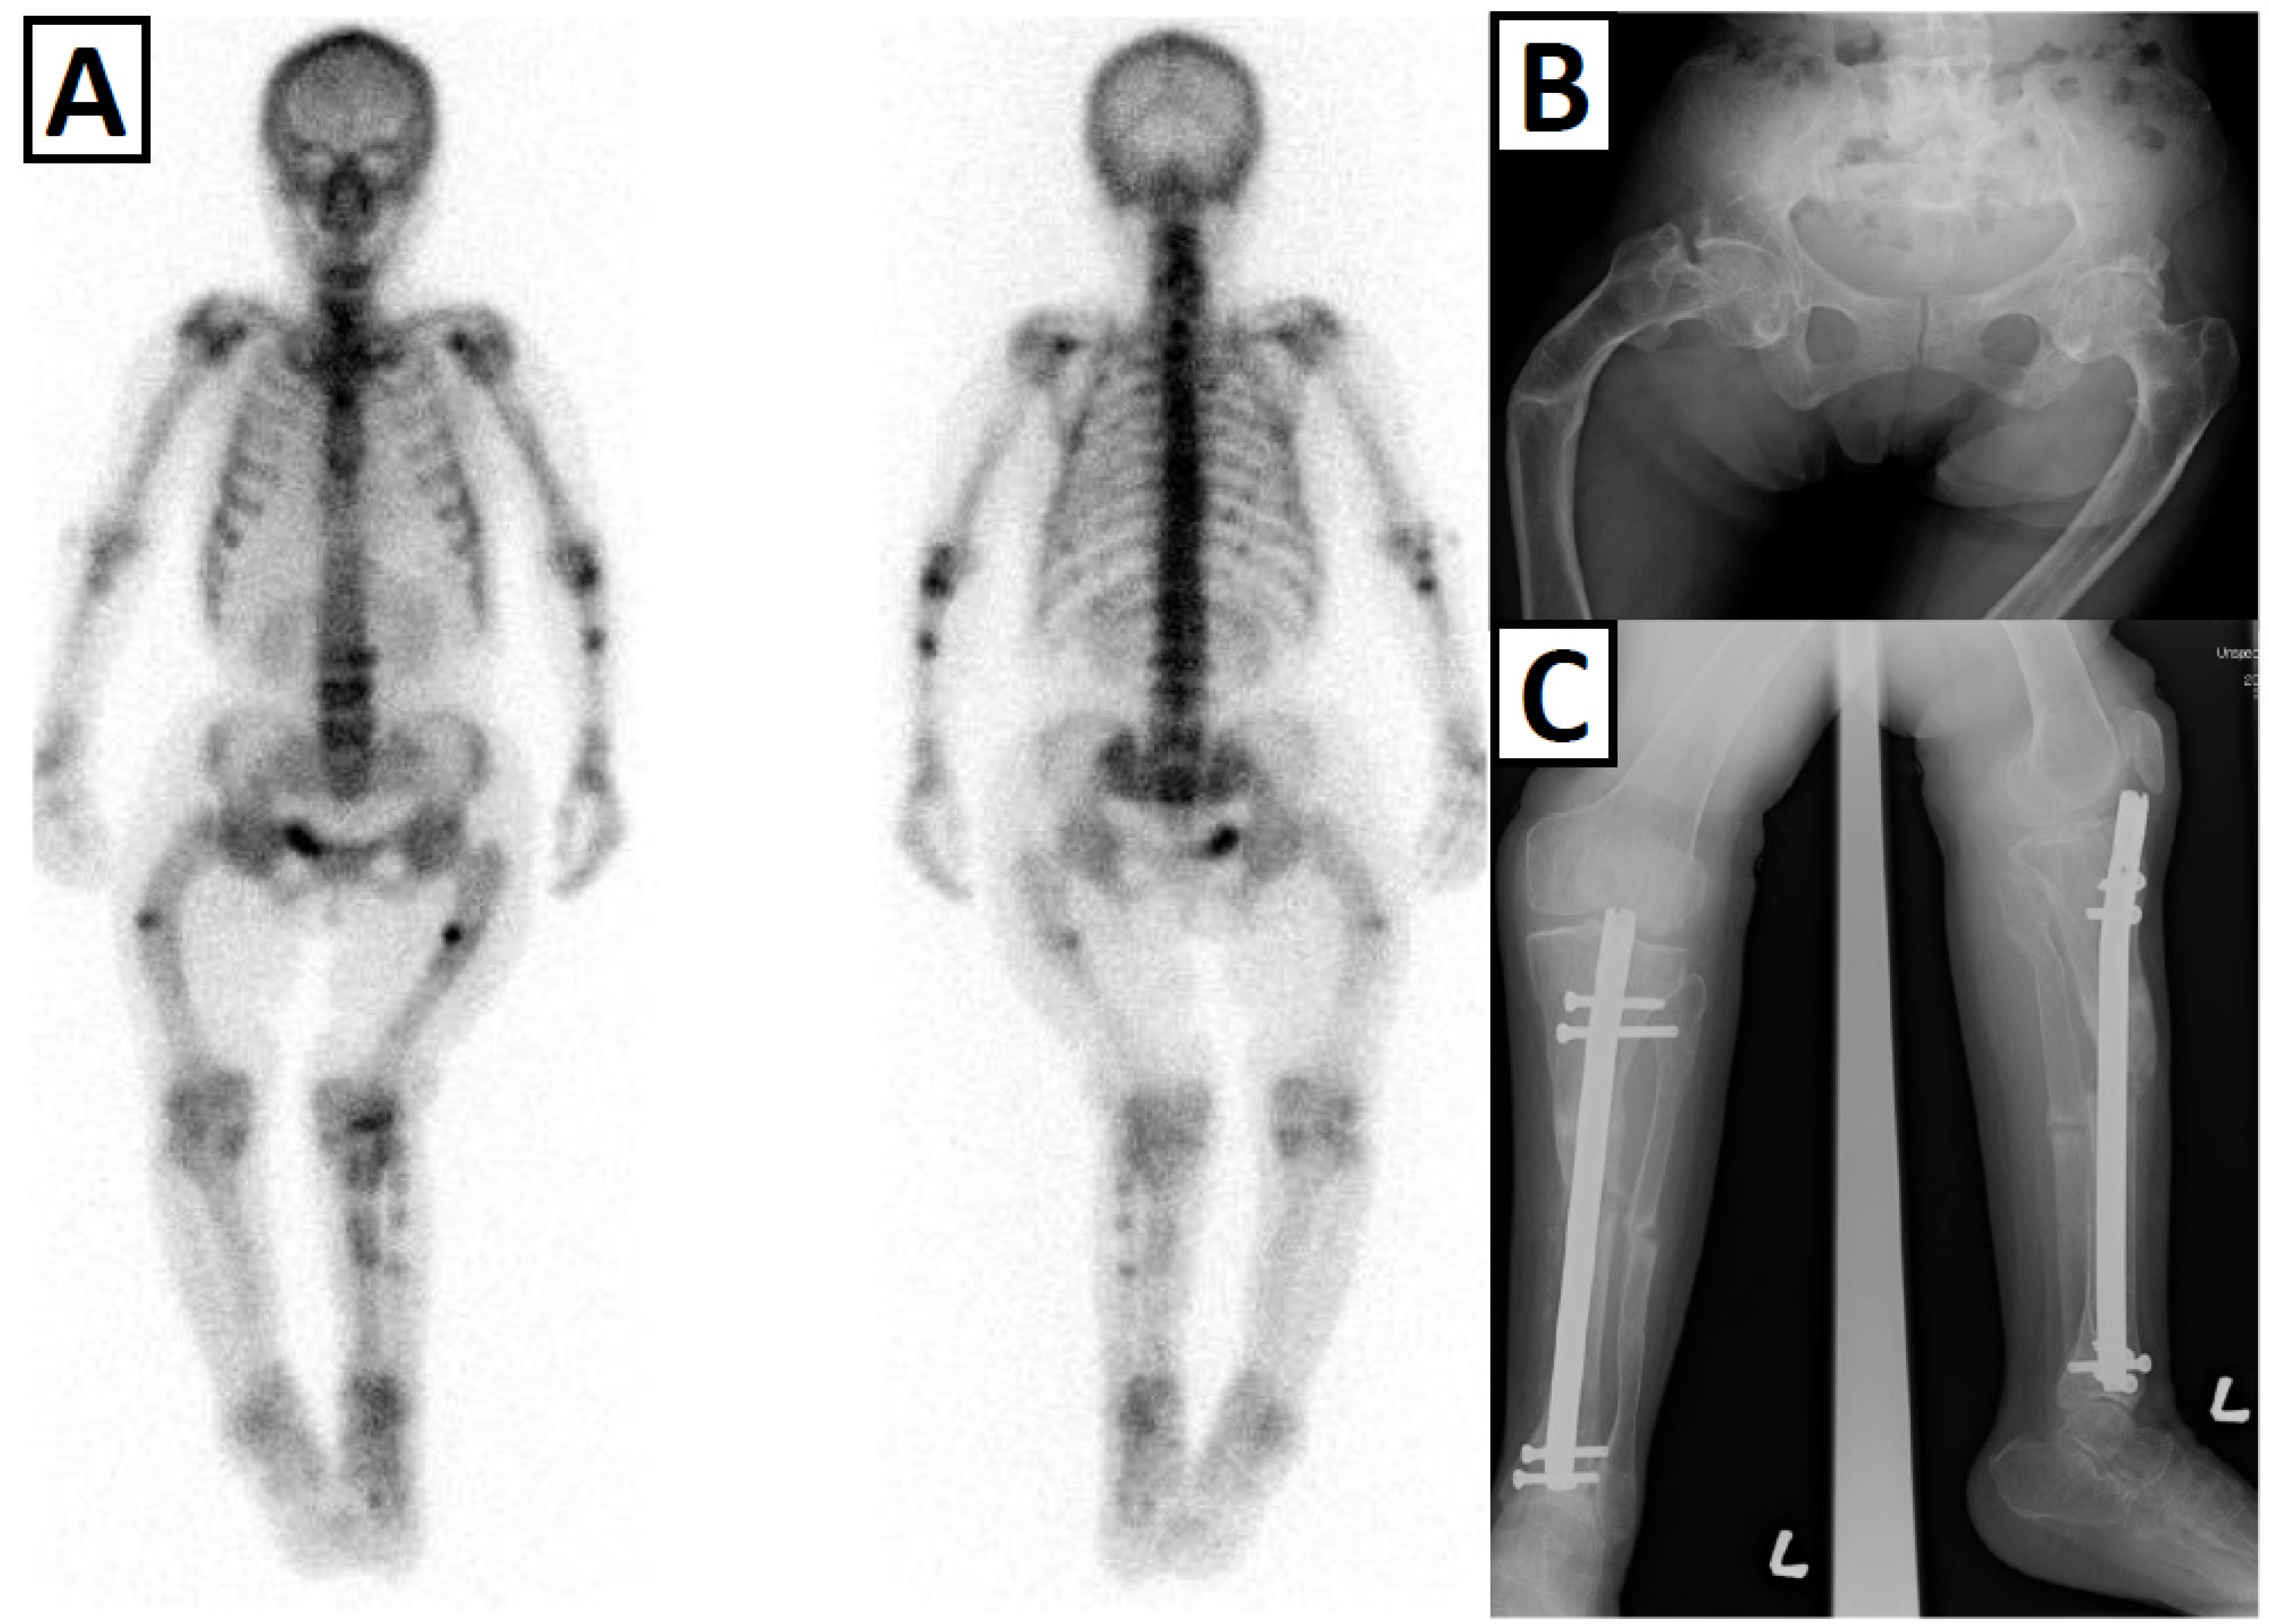

3.2. Lower Limb Deformity and Gait Difficulty

3.4. Bone Fragility